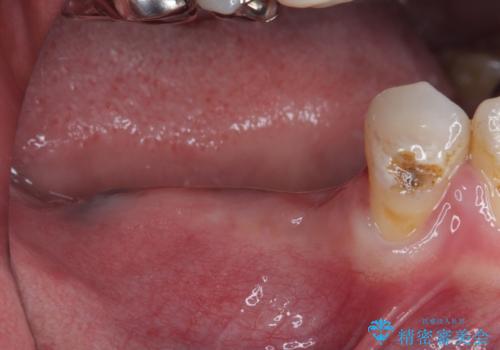

- ブリッジが装着されている奥歯がぐらぐらするとのことで来院された患者様です。

診察を行ったところ、手前の歯は歯根が破折しており、抜歯が必要な状態でした。

左右ともに臼歯部しか咬んでおらず、ブリッジの手前側の歯が破折したことで大きく揺さぶられてしまい、奥側の歯も周辺の歯が著しく吸収し、抜歯が必要な状態でした。

ブリッジの支台歯2本を抜歯し、反対側の咬合負担を軽減するために、通常よりも短い待機時間で2本のインプラントを埋入することとしました。